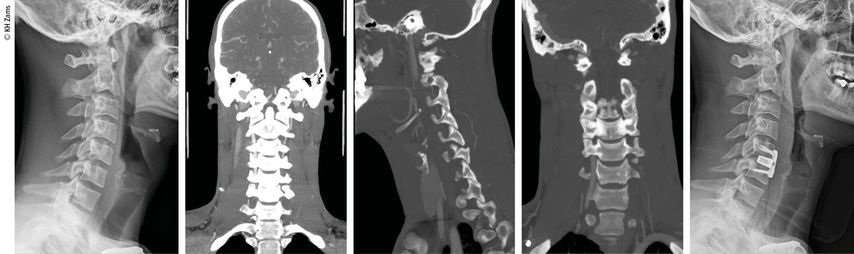

Abb. 3: Mann, 30a, Z.n. Snowboardsturz, Rotations-/Subluxationsverletzung C5/6 mit Dissektion der A. vertebralis r.; Zervikobrachialgie mit sensiblem Defizit; OP unter Heparintherapie, APT für 3 Monate

Abb. 4: Mann, 28a, Z.n. Schisturz; instabile Teardrop-Verletzung mit Dissektion A. vertebralis l.; Zervikobrachialgie mit Dysästhesie C6, mehrere kleine embolische Infarkte vertebrobasilär mit Koordinationsstörung; OP + Heparintherapie initial, anschließend APT